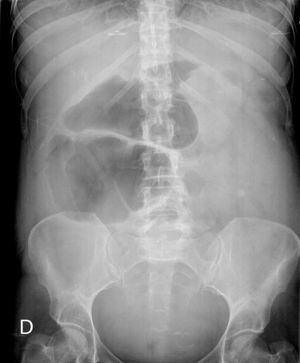

Pensando en el foco abdominal como responsable del shock y debido a la dificultad de la exploración, se solicitó TC toracoabdominal, que evidenció necrosis de la pared del hemicolon derecho (colon ascendente y transverso) por colitis isquémica no oclusiva (fig. 2). Con estos hallazgos se decidió cirugía urgente, encontrándose isquemia no solo del colon, sino también del útero y los anejos, por lo que se realizó histerectomía subtotal con doble anexectomía más colectomía subtotal, ampliando hasta 40cm de la válvula ileocecal. Se dejó ileostomía y fístula mucosa en colon descendente. Durante la intervención precisó de vasoactivos e inotropos a dosis altas, además de la trasfusión de hemoderivados (sangre, plasma fresco y plaquetas).

Las manifestaciones clínicas de este síndrome son numerosas, en función del principal órgano que se vea afectado, lo que dificulta el diagnóstico. En nuestra paciente, la situación de shock provocó una isquemia mesentérica no oclusiva, inicialmente en forma de colitis isquémica (la causa más frecuente de isquemia mesentérica9), pero con posterior afectación de otros órganos abdominales, como útero y anejos. La mortalidad de esta entidad puede llegar al 100% si no se trata de forma precoz y agresiva4. En nuestro caso, la realización del TC abdominal fue clave para el diagnóstico, ya que la cirugía inmediata, junto con el tratamiento antibiótico efectivo desde el primer momento, probablemente fueron las claves para la buena evolución posterior de la paciente.